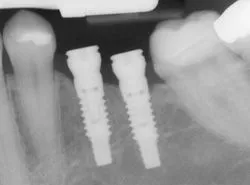

Conventional bridges and dentures are not fixed to the bone, and can therefore be unstable. This can make it difficult to eat or smile with confidence. Implants not only look more natural, but feel and act more like normal teeth, with a stronger biting force. And because they don't directly rely on neighboring teeth for support, implants don't compromise the health of your natural teeth. In fact, bridges are only expected to last seven to ten years, even less with root canals, whereas implants will typically last a lifetime.

imp xray